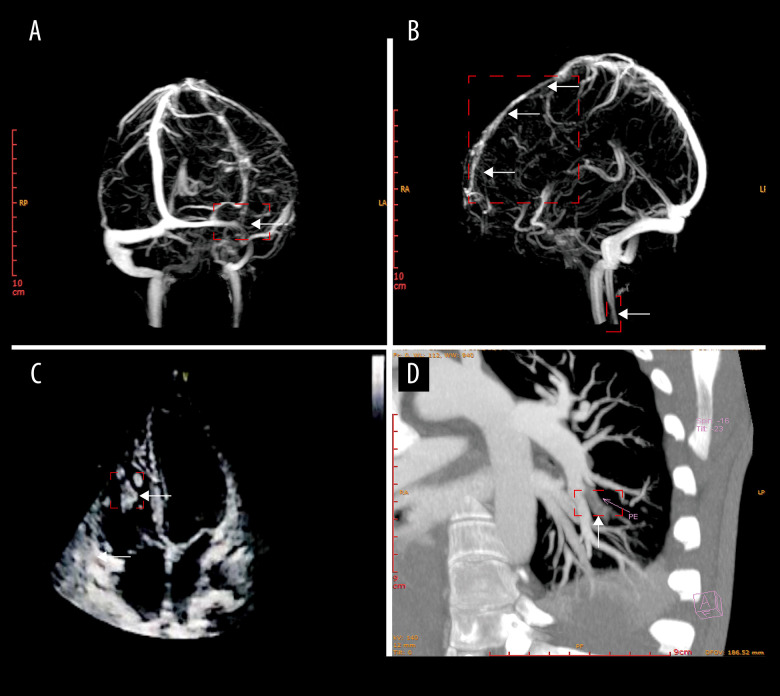

在高海拔地区,氧压降低和代偿性生理机制导致血液粘度和水肿增加。本报告描述了一名21岁男子在高海拔工作3天,并发脑静脉窦血栓形成、肺血栓栓塞和右心室血栓形成的病例。病例报告一名21岁男子在迅速上升到高海拔后第3天出现喉咙痛、咳嗽、呕吐和腹泻。抗感染治疗3天后效果甚微,第7天出现头痛、癫痫发作、头晕、视力模糊。他最终被诊断为脑静脉窦血栓形成(CVST)并发肺血栓栓塞(PTE)和右心室血栓形成。经低分子肝素和华法林治疗6个月后,预后良好。结论:本报告揭示了高原地区多发血栓事件的快速发展及其诊断和治疗方法。

BACKGROUND At high altitude, reduced oxygen pressure and compensatory physiological mechanisms lead to increased blood viscosity and edema. This report describes the case of a 21-year-old man working at high altitude for 3 days who developed cerebral venous sinus thrombosis, pulmonary thromboembolism, and right ventricular thrombosis. CASE REPORT A 21-year-old man developed sore throat, cough, vomiting, and diarrhea on the 3rd day after rapidly ascending to a high altitude. After 3 days of anti-infective treatment with minimal effect, he experienced headache, seizures, dizziness, and blurred vision on the 7th day. He was ultimately diagnosed with cerebral venous sinus thrombosis (CVST) complicated by pulmonary thromboembolism (PTE) and right ventricular thrombosis. After 6 months of treatment with low-molecular-weight heparin and warfarin, his prognosis was good. CONCLUSIONS This report shows the rapid progression of multiple thrombotic events at high altitude and the approaches to diagnosis and management.